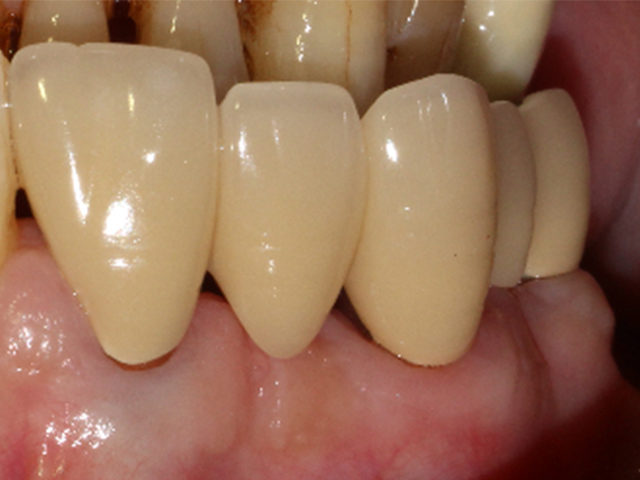

AFTER |

引っ張り上げた際についてきた歯周靭帯を切除して、歯質を高さ・厚み共に2ミリ以上確保することが出来ました。

引っ張り上げる期間は1ヶ月〜3ヶ月ほど、固定期間も1ヶ月〜3ヶ月ほどになります。

![]() |

引っ張り上げた歯に土台を立てて、被せ物を行いました。

根っこだけになり残すのが難しい歯でしたが、無事に歯を残すことができました。

現在治療後6年経過していますが、問題なく機能しています。